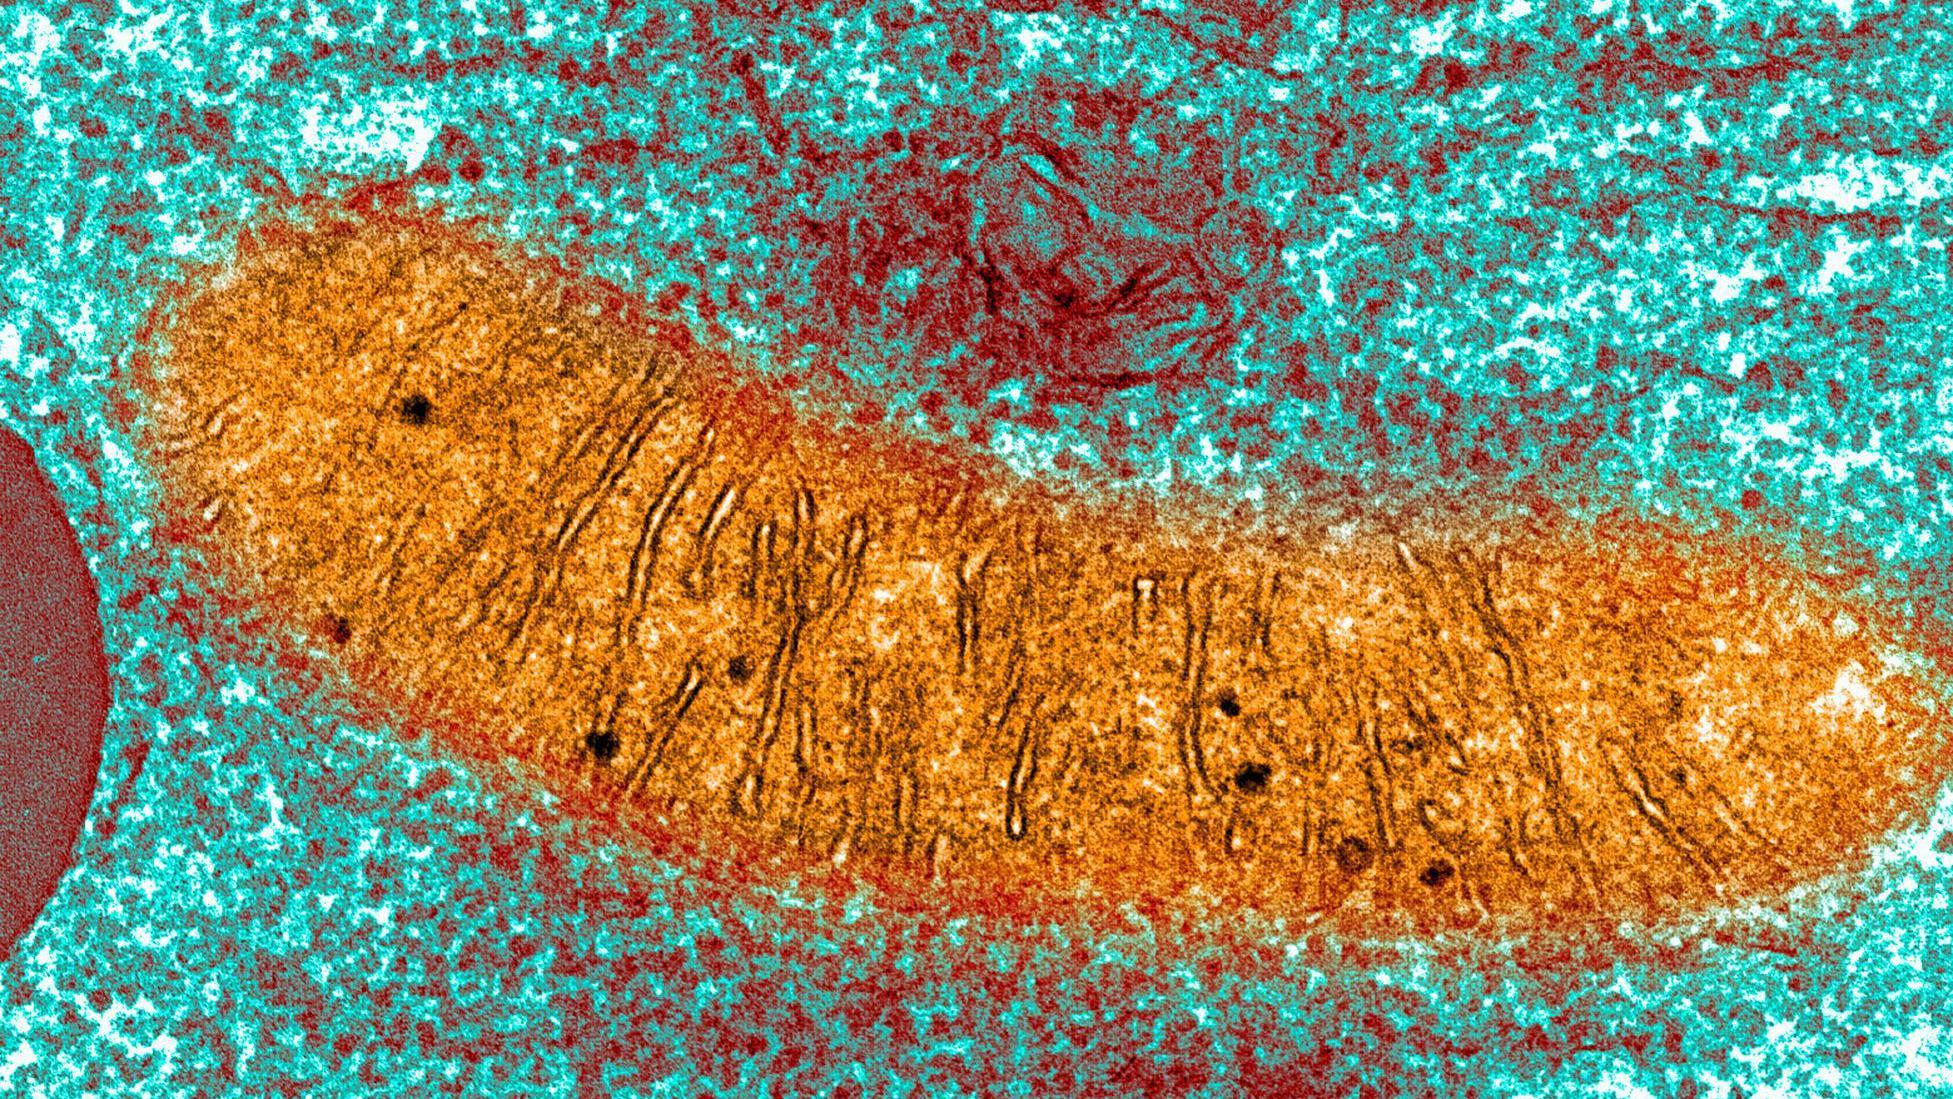

Mitohondrije su sićušne strukture unutar gotovo svake naše ćelije.

One su razlog zbog kojeg dišemo, jer koriste kiseonik da pretvore hranu u oblik energije koju telo koristi kao gorivo.

Poremećaj funkcije mitohondrija može da ostavi telo bez dovoljno energije da održi rad srca, a može da urzokuju i oštećenja mozga, epilepsiju, slepilo, slabost mišića, i otkazivanje organa.